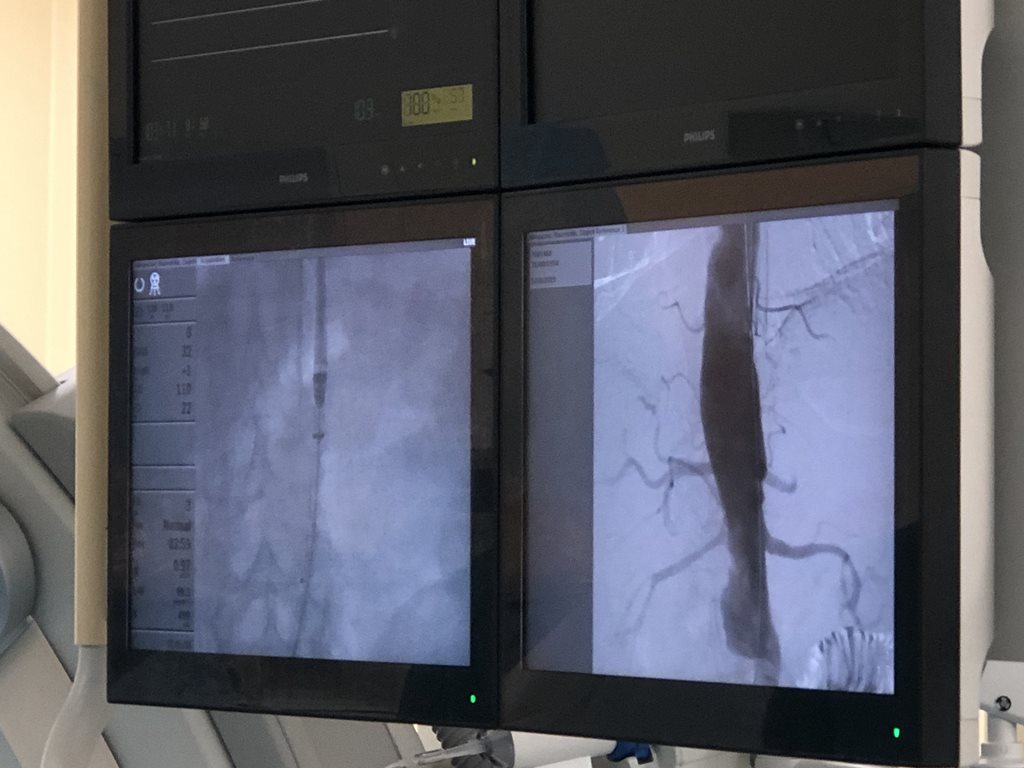

5 октября впервые в Поволжском федеральном округе в отделении сосудистой хирургии Центра Экстренной медицины (7ГКБ МЗ РТ) произведена инновационная высокотехнологичная операция: «Эндопротезирование аорты с применением эндоваскулярной системы фиксации Aptus Heli-FX».

Еще в ближайшем прошлом пациентам со сложной анатомией и короткой проксимальной шейкой аневризмы возможно было выполнить только открытую полостную операцию. Но данная категория операций  сопровождалась высоким процентом летальности в интра- и постоперационном периоде. Использование малоинвазивной методики позволяет значительно расширить возможности эндопротезирования аневризмы аорты и выполнить больший охват пациентов, с целью улучшения качества их жизни и снижения смертности от разрыва аневризмы, что соответсвует основным целям снижения смертности от сердечно-сосудистых заболеваний Национального проекта «Здравоохранение».